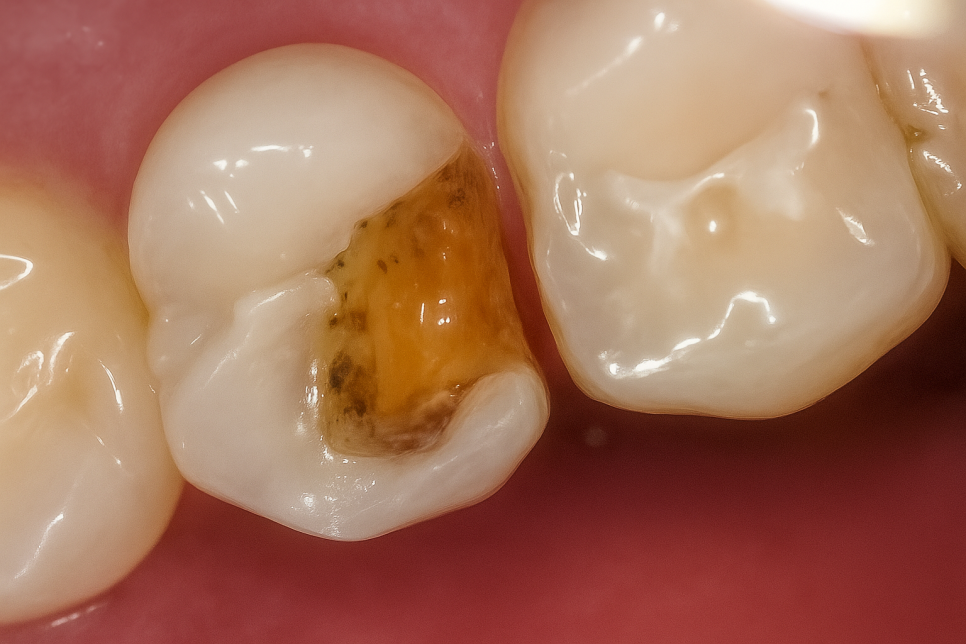

인접면 우식증

치아 사이 틈은 매우 긴밀합니다.

그래서 칫솔모가 여기까지 닿지 않아 치실이나 치간 칫솔을 써야 되는데,

만약 이 사이가 관리되지 못해 음식 찌꺼기가 오랫동안 껴 있으면

인접면 우식증 즉, 치아 사이도 썩을 수 있습니다.

눈으로 잘 안 보이는 곳이라 초기에 발견하기 어려우며,

대개 깊게 진행되어 통증을 느낀 후 문제가 있음을 깨닫게 됩니다.

그런데 문제는 이 사이(인접면)은

음식을 씹을 때 사용하는 교합면과 달리

겉질이 얇아 안쪽 속질까지 빠르게

이가 썩어들어간다는 점입니다.

또한 눈에 잘 안 보이기 때문에 초기에 발견하더라도

기구가 닿을 수 있도록 멀쩡한 치아를 많이 삭제해야 되므로

미리 예방하는 것이 정말 중요하죠.